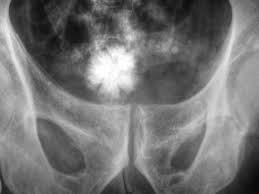

Močové kameny vznikají krystalickým usazováním určitých látek (především vápenatých solí a kyseliny močové), které jsou za normálního stavu rozpustné v moči. Tyto usazeniny se postupem času zformují do pevných kamínků, které putují a mohou zablokovat odvod oči.

Močové kameny se mohou nacházet v ledvinách, močovodu, močovém měchýři nebo močové trubici. Když putují z ledvin močovodem do měchýře, dochází k ledvinové kolice, která je extrémně bolestivá.

Většina močových kamenů (80 %) je tvořeno z vápenatých solí, jako kalcium oxalátu nebo kalcium fosfátu, následují urátové kameny z kyseliny močové (15 %), vzácnější jsou struvitové kameny z hořčíku, amonia a fosfátu, jen zřídka se vyskytují cystinové kameny.

Močové kameny se mohou objevovat jednotlivě nebo ve skupinách.

Močové kameny vznikají z minerálů rozpuštěných v moči. Typicky opouští tělo spolu s močí a mnoho kamenů nevyvolá žádné symptomy. Pokud se močový kámen zvětší na velikost 2 až 3 mm před močovým měchýřem, mohou způsobit zácpu močovodu.